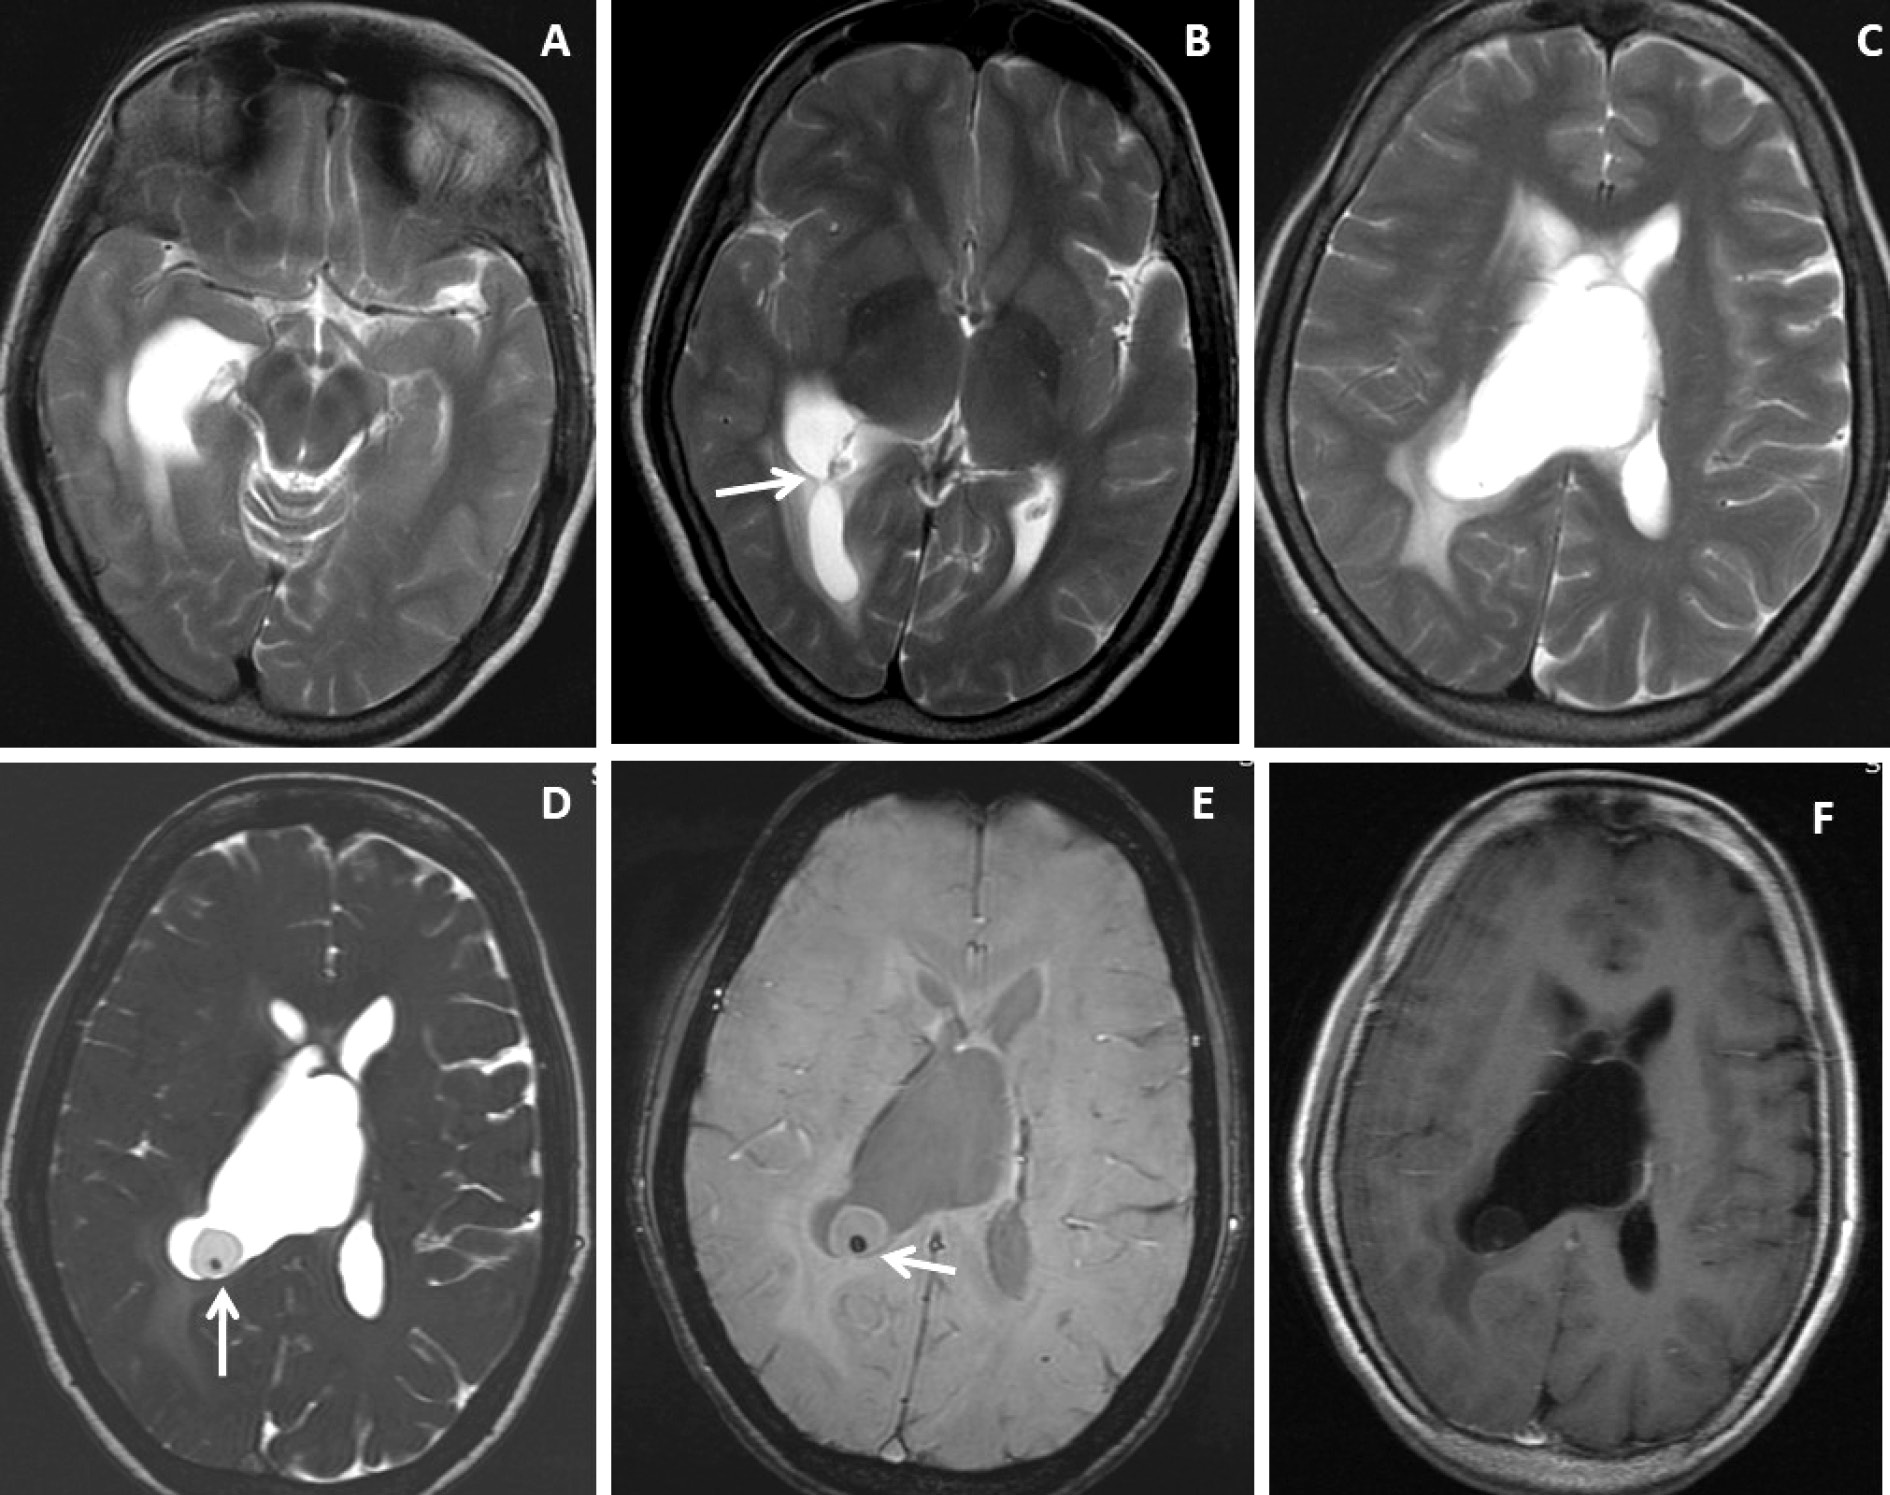

Figure 1. Brain magnetic resonance imaging of 52 years female with headache and vomiting. (A-C) Axial T2WI images show asymmetrical hydrocephalus with entrapment of temporal horn of the right lateral ventricle with narrowing / adhesion in the trigone of the lateral ventricle (arrow) with surrounding periventricular CSF seepage. (D) Heavily T2-weighted image shows an intraventricular neurocysticercus lesion with a T2 hypointense scolex within (arrow). (E) Axial susceptibility-weighted image shows nodular blooming of the calcified scolex within the thin wall IVNCC (arrow). (F) Axial post-gadolinium T1W image shows thin smooth peripheral cyst wall enhancement with the smooth ependymal enhancement of the asymmetrically dilated lateral ventricle.

T2WI, DRIVE and SWI visibility score of the scolex of intraventricular neurocysticercosis (IVNCC): In 10patients with intraventricular neurocysticercosis, the scolex was distinctly visualized (visibility score 2) in 2(20%) patients on T2WI, 8(80%)patientson 3D-DRIVE (Figure 1) and 3(30%) on SWI sequence (Figure 1). For identification of scolex in intraventricular neurocysticercosis with a visibility score of 2, the 3D-DRIVE sequence had a sensitivity of 80% followed by 30% with SWI and 20% with T2W images. The poorly visualized scolex of intraventricular neurocysticercosis (visibility score 1) noted in 2 (20%) patients on 3D-DRIVE, 5(50%)patientson SWI and 2(20%) on T2W sequence [Table 2].

T2WI, DRIVE and SWI visibility score of the wall of intraventricular neurocysticercosis: Of 10patients with IVNCC, the cyst wall was distinctly visualized (visibility score 2) in 1 (10%) patient on T2WI, 8 (80%) patientson 3D-DRIVE (Figure 1 and 2) and 6 (60%) patients on SWI sequence. For identification of wall of IVNCC with a visibility score of 2, the 3D-DRIVE sequence had a sensitivity of 80% followed by 60% with SWI and 10% with T2W images. Cyst wall calcification was identified in 1(10%) patient on SWI. Poorly visualized wall of intraventricular neurocysticercosis (visibility score 1) noted in 2(20%) patients on 3D-DRIVE, 4(40%) patients on SWI and 4(40%) on T2W sequences [Table 2].